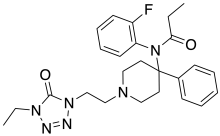

Anilidopiperidines

- 3-Allylfentanyl

- 3-Methylfentanyl

- 3-Methylthiofentanyl

- 4-Phenylfentanyl

- Alfentanil

- α-Methylacetylfentanyl

- α-Methylfentanyl

- α-Methylthiofentanyl

- Benzylfentanyl

- β-hydroxyfentanyl

- β-hydroxythiofentanyl

- β-Methylfentanyl

- Brifentanil

- Butyrfentanyl

- Carfentanil

- Fentanyl

- Lofentanil

- N-Methylcarfentanil

- Mirfentanil

- Ocfentanil

- Ohmefentanyl

- Parafluorofentanyl

- Phenaridine

- R-30490

- Remifentanil

- Sufentanil

- Thenylfentanyl

- Thiofentanyl

- Trefentanil

Structures